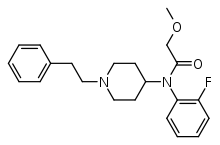

Anilidopiperidines

- 3-Allylfentanyl

- 3-Methylfentanyl

- 3-Methylthiofentanyl

- 4-Phenylfentanyl

- Alfentanil

- α-Methylacetylfentanyl

- α-Methylfentanyl

- α-Methylthiofentanyl

- Benzylfentanyl

- β-hydroxyfentanyl

- β-hydroxythiofentanyl

- β-Methylfentanyl

- Brifentanil

- Butyrfentanyl

- Carfentanil

- Fentanyl

- Lofentanil

- N-Methylcarfentanil

- Mirfentanil

- Ocfentanil

- Ohmefentanyl

- Parafluorofentanyl

- Phenaridine

- R-30490

- Remifentanil

- Sufentanil

- Thenylfentanyl

- Thiofentanyl

- Trefentanil

Structures